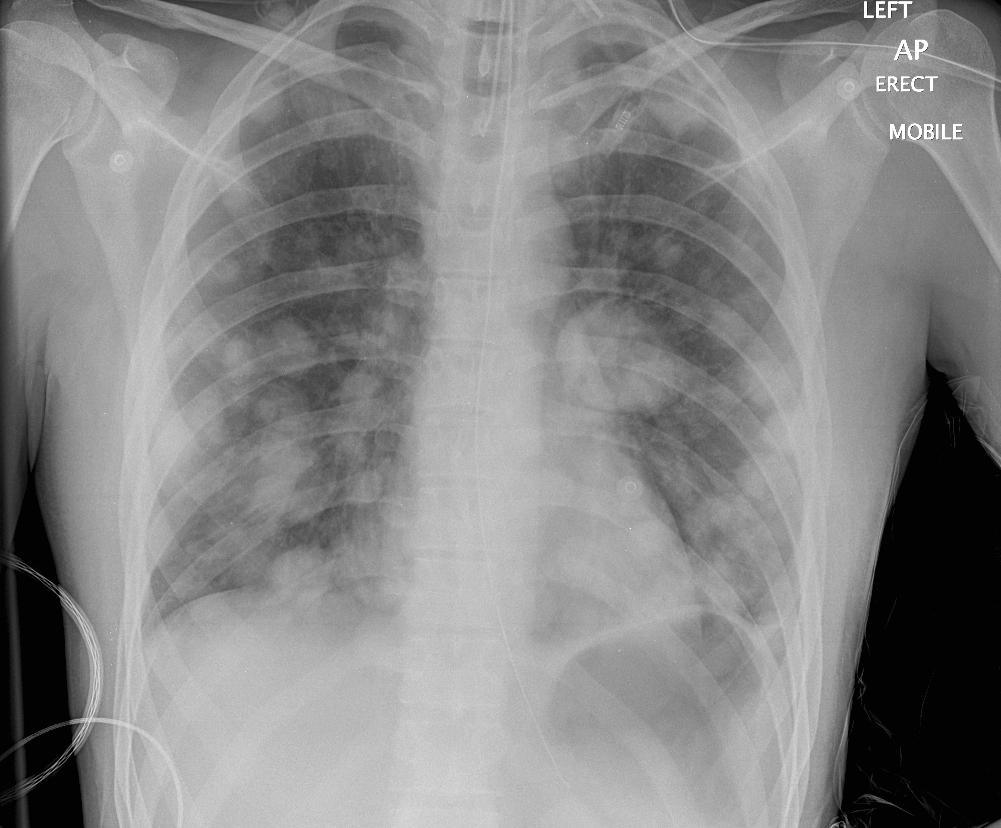

RMB Intubation, Left Collapse